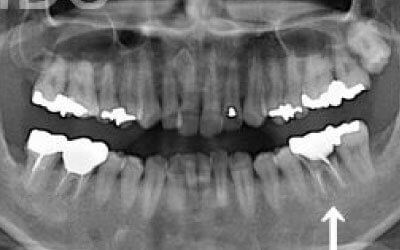

CTを使うと、骨や歯の状態を立体的に確認でき、正確な距離も測定できます。

骨の厚さや傾き、神経の位置などを事前に詳しく把握することで、安全にインプラント治療を行うことができるのです。

2 神経を傷つけるリスク

顎の骨の中には神経が通っており、インプラント治療の際にそれを傷つけてしまうリスクがあります。

しかし、当院では事前にCT撮影を行い、神経までの距離を三次元的に正確に把握した上で治療計画を立てるため、リスクをしっかり回避できます。

さらに、骨を削りすぎないようにするための専用のストッパーも導入しており、安全性には十分に配慮しています。

4)骨の状況をしっかり把握するためにも、CT撮影が必須となります。